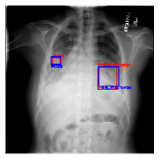

CXR8 [21] is one of the most commonly accessible radio-logical examination for many lung diseases. The data consists of 112,120 images collected by 30,805 patients. As shown in Table I, nine class labels of normal state and eight diseases including cancer are defined for classification. The data is divided into training set and test set, and the classification accuracy and ROC curve with several well-known deep network such as VGG16, GoogLeNet, and ResNet, are reported on the original paper [21]. In addition, 984 Bounding Boxes (B-Box) are provided for localization. Fig. 5 shows image examples of CXR8. The red rectangle in the image shows given B-Box.

Refer to caption

(a) Atelectasis

(b) Mass

Figure 5: Image examples of CXR8